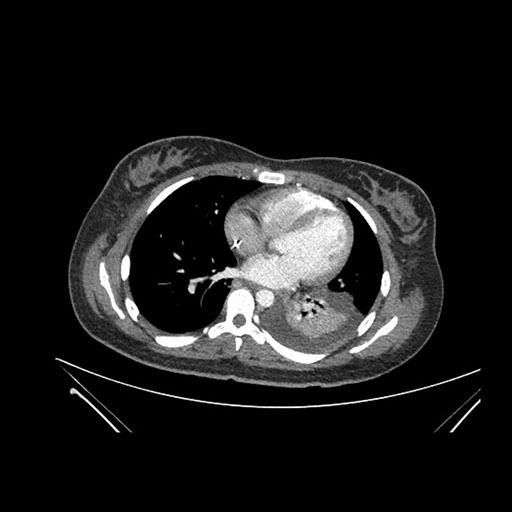

Axial Arterial

Axial Venous